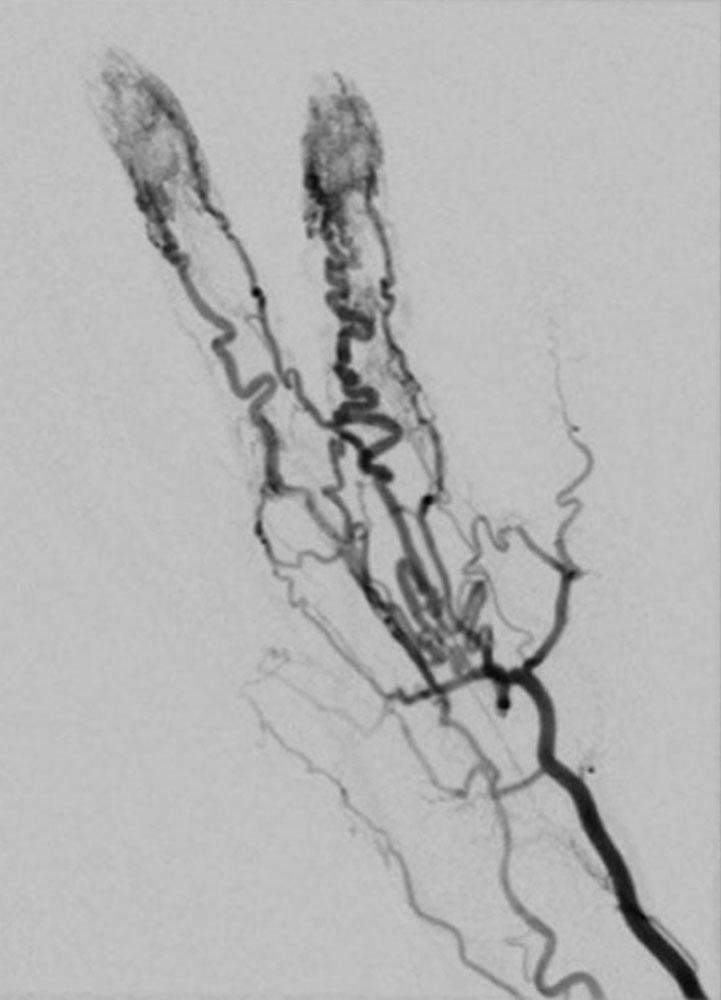

In most cases, catheter angiography is only performed as part of a minimally invasive treatment. The arteries supplying the nidus are often twisted, dilated and sometimes aneurysmally dilated. As a result of the arteriovenous shunt connections, there is immediate, early contrast filling of the dilated veins.

Peripheral arteriovenous malformations can be classified according to their angiographic anatomy, particularly their venous outflow.

Unlike venous malformations, there is characteristically no extensive contrast agent accumulation or contrast agent stasis in the form of "pooling". A so-called “blush” in the sense of a very fine fistulous nidus may appear at a very early stage of an arteriovenous malformation, for example in children, and this appears similar to a vascular tumor without a space-occupying mass.